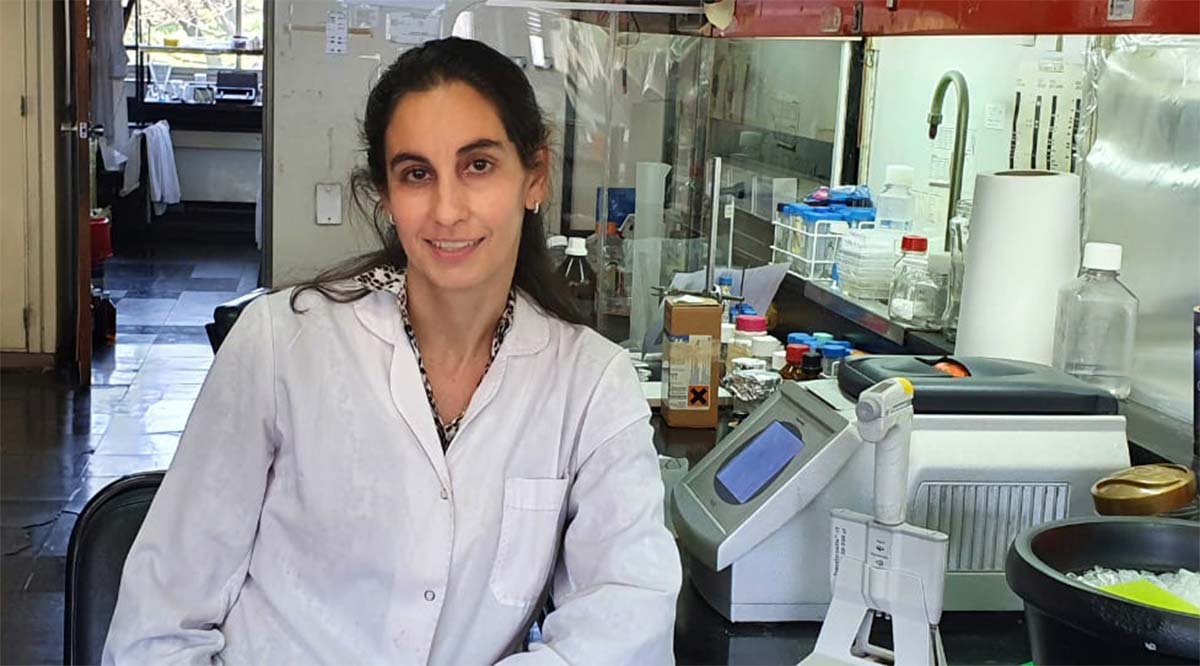

Gabriela Camporeale, investigadora de la Fundación Instituto Leloir (FIL), recibió un subsidio de la Fundación Florencio Fiorini para revelar un mecanismo clave en la replicación del virus sincicial respiratorio, que contagia a dos tercios de los niños en su primer año de vida.

Para entender la intimidad del modus operandi viral y ayudar a inspirar el desarrollo de medicamentos y métodos diagnósticos, Camporeale recibió un subsidio de la Fundación Florencio Fiorini y la Academia Nacional de Medicina.

“Estos fondos son de gran ayuda para realizar experimentos de laboratorio que arrojen luz sobre el comportamiento del virus a nivel molecular en su interacción con células en procesos de infección”, indica Camporeale, integrante del Laboratorio “Estructura-Función e Ingeniería de Proteínas” que lidera Gonzalo de Prat Gay en la FIL.

“Conocer los factores genéticos y moleculares que regulan la multiplicación del virus es el paso previo para desarrollar estrategias terapéuticas eficaces”, afirma Camporeale, también investigadora del CONICET.